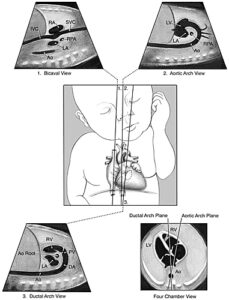

Сагиттальный вид верхней и нижней полой вены ( 1 ) , дуги аорты ( 2 ) и дуги аорты ( 3 ) . Угол сканирования между дугой аорты и грудноым отделом аорты колеблется в пределах от 10 ° до 19 ° во время беременности, как показано на виде диаграммы 4 — камеры (Эспиноза J , Gotsch F , Kusanovic JP и др изменения геометрии сердца плода в гестации: последствия для 3- и 4 -мерная эхокардиография плода J Med 2007 Ультразвук). Ао или Desc Ао показывает нисходящую аорту ; Ао корень, корень аорты ; DA , артериальный проток ; IVC , нижняя полая вена ; LA, левое предсердие; LV , левый желудочек ; PV , легочный клапан ; RA , правое предсердие; RPA , правой легочной артерии ; RV , правый желудочек; и SVC , верхняя полая вена.

Низкие и высокие виды короткой оси сердца плода. Ао обозначает аортальный клапан; DA , артериальный проток ; LV , левый желудочек ; PA, легочной артерии ; RA , правое предсердие; и RV, правый желудочек.